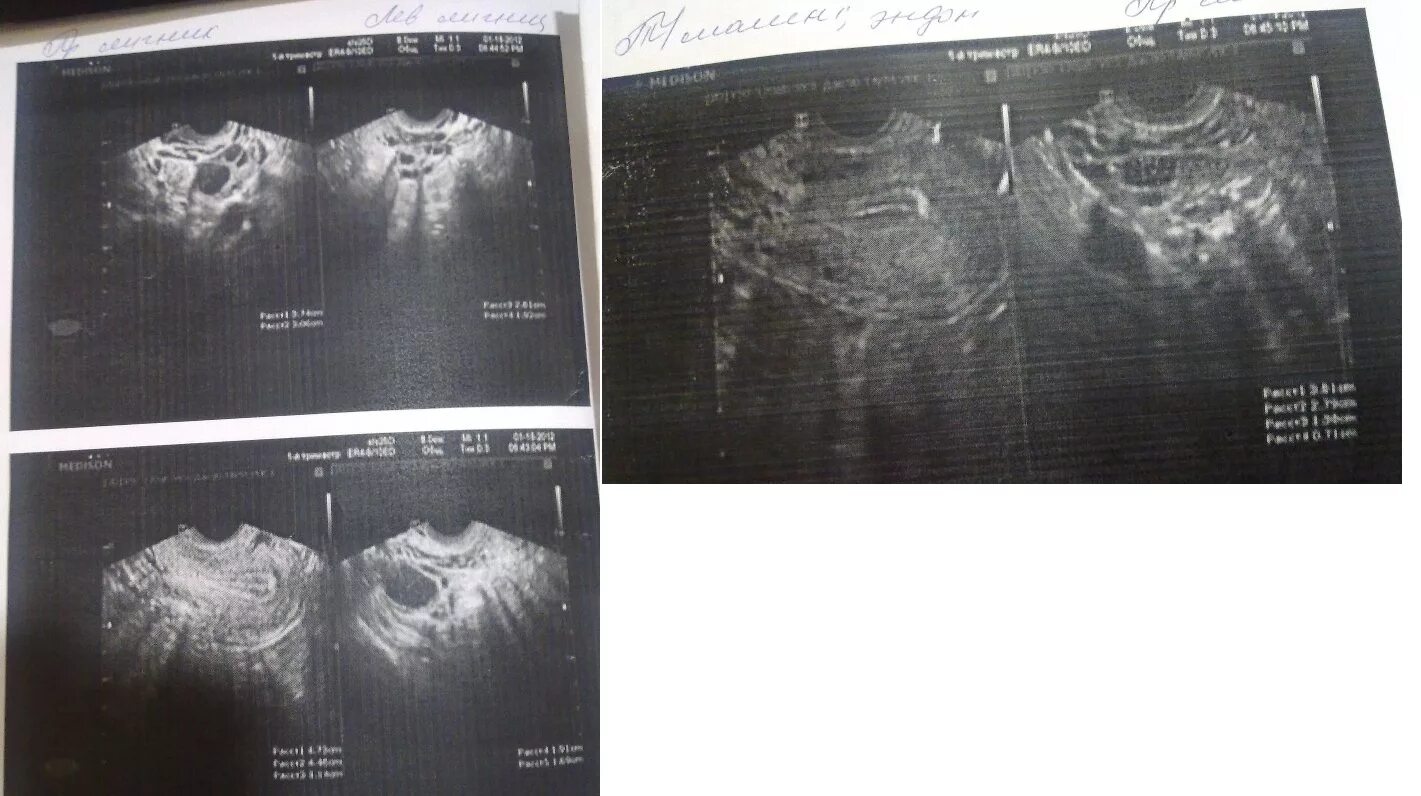

Эхо 7 мм